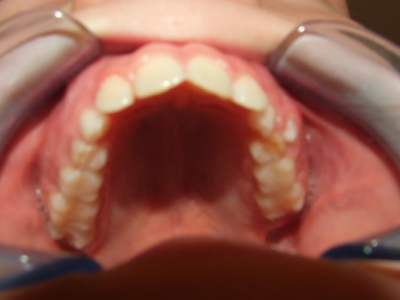

eindfoto

Beschrijving

Leeftijd bij aanvang: 10 jaar

Bonded Hyrax + volledig vast onderkaak

Volledig vast bovenkaak + expander

Wrap + c-c bar onderkaak

Leeftijd bij afname: 12 jaar